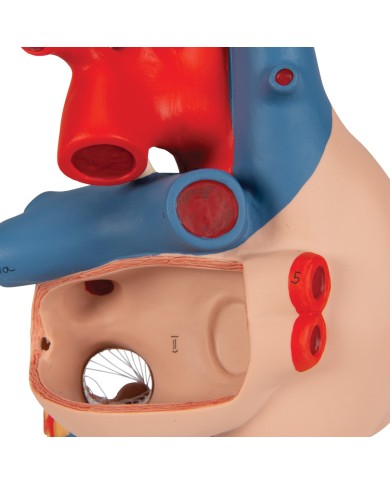

I modellini anatomici di cuore umano sono strumenti indispensabili per uno studio corretto dell'anatomia del cuore umano.

Per una migliore comprensione delle strutture anatomiche del cuore sono stati realizzati anche dei modelli anatomici di cuore ingrandito, si va dai piccoli ingrandimenti fino ai modelli di cuore per la formazione in aula, come il modello anatomico di cuore gigante prodotto da 3B Scientific: un modello di cuore ingrandito di ben otto volte.

Su Tuttoanatomia trovi la più vasta selezione online, certamente abbiamo il modello di cuore più adatto alle tue esigenze. I cardiologi e gli studenti acquistano i modelli anatomici di cuore umano per studiare nei minimi dettagli la struttura anatomica del cuore umano, ma anche per dare spiegazioni ai propri pazienti, per illustrare visivamente la patologia di cui sono affetti, ed il tipo di intervento che si intende eseguire durante la terapia. Le quotazioni su Tuttoanatomia sono le più convenienti del mercato e la qualità dei prodotti è davvero eccezionale, in modo da offrirti un rapporto qualità prezzo incomparabile.